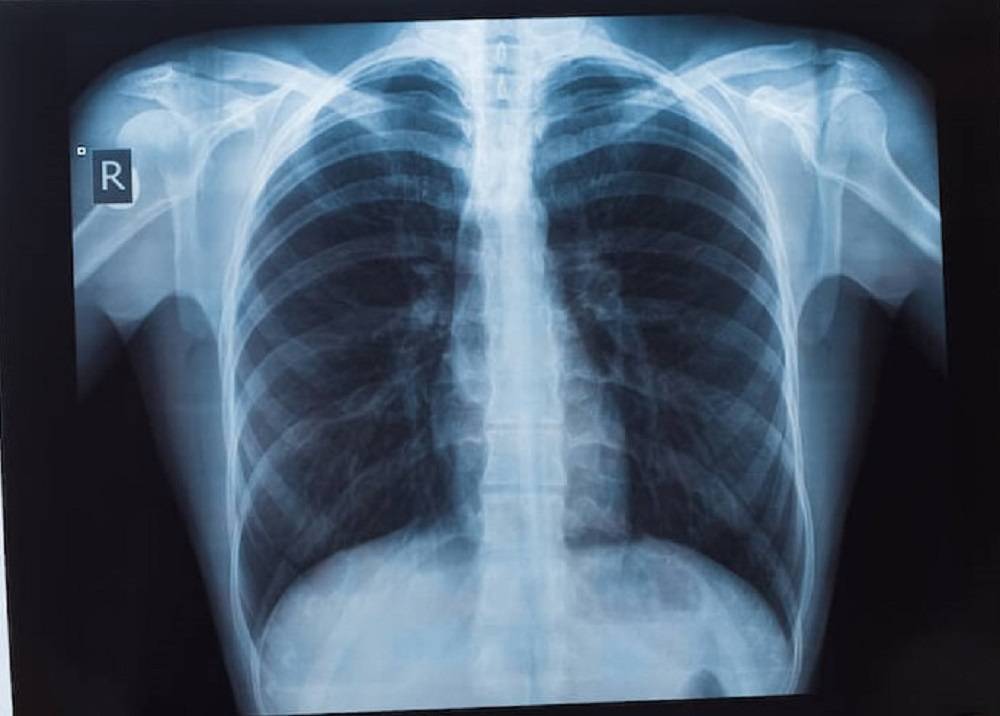

รศ.นพ.ศิระ เลาหทัย ศัลยแพทย์ทรวงอกจากศูนย์ผ่าตัดส่องกล้อง โรงพยาบาลวชิรพยาบาล กล่าวว่า มีคำถามยอดฮิตที่ว่า “เจอจุดที่ปอด (lung nodule) มีโอกาสเป็นมะเร็งกี่เปอร์เซ็นต์?” นั้นหลายครั้งที่เราไปตรวจสุขภาพแล้วพบเจอฝ้าขาว เมื่ออ่านผลรังสีวินิจฉัยพบเจอความผิดปกติในฟิล์มเอกซเรย์ปอด ทั้ง ๆ ที่เรายังไม่มีอาการผิดปกติใด ๆ เลย สิ่งที่สำคัญที่สุด ก็คืออย่าเพิ่งตกใจเราต้องหาสาเหตุของจุดที่เกิดขึ้นมีจริงหรือไม่ โดยวิธีการที่หาสาเหตุที่ดีที่สุดคือการทำเอกซเรย์คอมพิวเตอร์(CT scan) แต่ไม่ควรที่จะทำเอกซเรย์ซ้ำ เพราะไม่เกิดประโยชน์

เนื่องจากการทำฟิล์มเปรียบเสมือนการถ่ายภาพ 2 มิติ เห็นแค่ด้านหน้า-หลัง ส่งผลทำให้เกิดผลภาพลวงได้บ่อย เปรียบเทียบกับการทำเอกซเรย์คอมพิวเตอร์เห็นรายละเอียด เป็นลักษณะของก้อนเนื้อว่าสงสัยมะเร็ง หรือไม่ รวมทั้งมีจริงหรือไม่ หากการทำเอกซเรย์คอมพิวเตอร์ CT scan ไม่มีจุดหรือไม่พบจุด บางที่สิ่งที่เราเห็นจากฟิล์ม คือเงาที่ซ้อนทับกัน เนื่องจากมุมภาพ กรณีนี้มั่นใจได้ ว่าไม่มีอะไร ใช้ชีวิตปกติ ติดตามตรวจสุขภาพประจำปี ในทางกลับกัน เมื่อใดหากเราได้ทำเอกซเรย์คอมพิวเตอร์แล้วเจอว่ามีจุดที่ปอดที่ปอดจริงๆ โดย สาเหตุอาจเกิดได้จาก 1) มะเร็ง (อาจจะเป็นมะเร็งปอดหรือมะเร็งจากที่อื่นกระจายมา) 2) วัณโรคและ 3) อย่างอื่น ๆ เช่น เนื้องอกธรรมดาของปอด หรือ ในช่องทรวงอก

ซึ่งปกติเมื่อทำเอกซเรย์คอมพิวเตอร์ (CT scan) มักจะเจอจุดโอกาสเป็นมะเร็งแค่ 1% แนะนำควรเจอแพทย์ที่มีความเชี่ยวชาญ เช่น หมอโรคปอดหรือหมอผ่าตัดปอด เพื่อจะดูความน่าจะเป็น หรือติดตามอย่างไรดี ในกรณีที่เรียกว่าแจ็คพอตแตก ก็คือเมื่อใดที่สงสัยว่าก้อนเนื้อ อาจจะเป็นเนื้อร้ายการเอาชิ้นเนื้อเป็นสิ่งที่สำคัญที่สุดโดยสามารถทำได้หลายวิธี เช่น การส่องกล้องผ่านหลอดลม (Bronchoscope)โดยการเจาะเอาชิ้นเนื้อโดยการทำเอกซเรย์คอมพิวเตอร์ (CT guide Biopsy) ผ่าตัด (Surgical biopsy) ดังนั้นแนะนำการทำเอกซเรย์คอมพิวเตอร์ปอด (CT scan) จึงเป็นการฉายรังสีเอ็กซ์ไปที่ส่วนของหน้าอกหรือปอด โดยภาพจากการฉายรังสีนั้นจะถูกบันทึกลงในแผ่นฟิล์มที่มีความละเอียดสูง ซึ่งแพทย์จะใช้ในการตรวจวินิจฉัยความสมบูรณ์ของอวัยวะภายใน ทั้งทรวงอก ปอด และโครงสร้างข้างเคียง

อีกทั้ง ปัจจุบัน วิวัฒนาการเราสามารถทำ Low dose CT การเอกซเรย์คอมพิวเตอร์ใช้รังสีต่ำ จึงเป็นการตรวจอย่างหนึ่งที่นิยมใช้กันมาก ในการคัดกรองมะเร็งปอดเพราะเป็นการตรวจที่ง่ายและสามารถคัดกรองได้เบื้องต้น ไม่เป็นอันตรายเพราะใช้รังสีที่มีปริมาณน้อย โดยรูปแบบการทำงานของเครื่องเอกซเรย์ปอดจะใช้เพื่อให้ได้ภาพรังสีของภาพภายในปอดทั้งหมด ปัจจุบันประเทศไทยได้ทำ“การเอกซเรย์ปอด” เป็นเครื่องมือสำคัญในการวินิจฉัยระบบการทำงานอวัยวะภายในที่ผิดปกติ ไม่ว่าจะเป็นการตรวจเช็คตั้งแต่บริเวณอวัยวะส่วนทรวงอกจนไปถึงส่วนของโครงสร้างกระดูกที่ครอบคลุมบริเวณปอดและหัวใจ ซึ่งเป็นอวัยวะสำคัญในการดำเนินชีวิตของมนุษย์ ดังนั้นการตรวจเอกซเรย์ปอด (การตรวจเช็คอวัยวะภายในของบริเวณส่วนทรวงอกที่ประกอบไปด้วยโครงกระดูก ปอดและหัวใจเป็นหลัก และได้มีการพัฒนาให้ภาพฉายรังสีถูกสแกนเป็นระบบดิจิตอล ทำให้ผู้ป่วยได้รับการวินิจฉัยที่แม่นยำมากขึ้น